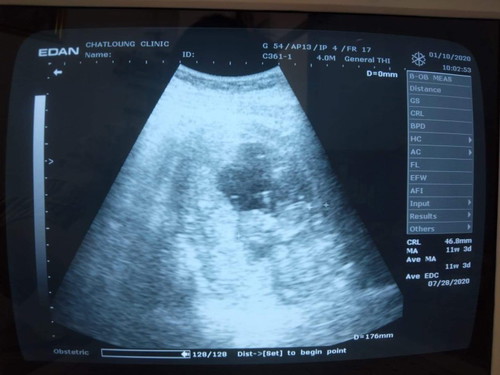

ท้องแรก 11w+3 น้ำหนักแม่ลงค่ะเป็นอะไรมั้ยคะ

ท้องแรกๆหนัก61 ตอนนี้ลงมาเป็น60 ต้องบำรุงยังไงบ้างคะ